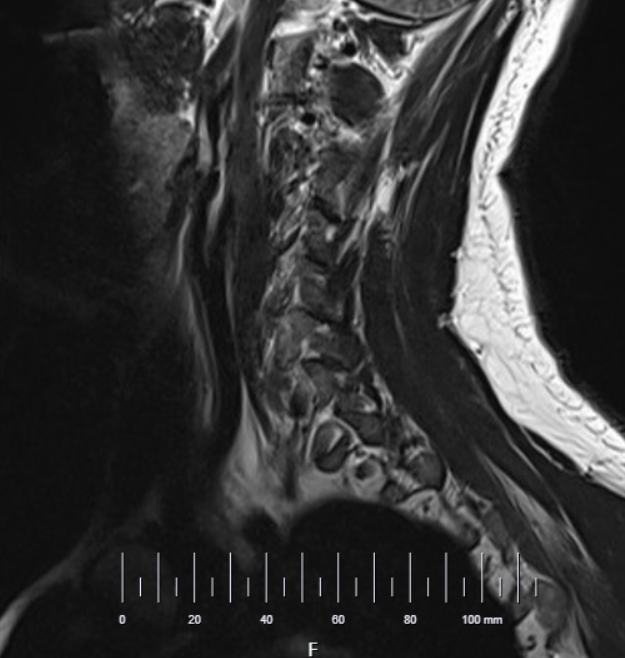

Scale Ruler in viewport

Users can now enable a scale ruler from the Imaging Study settings to display it at the bottom of the viewport, offering a clear visual guide for accurate image measurements.

Imaging study settings:

Scale ruler enabled in viewport: